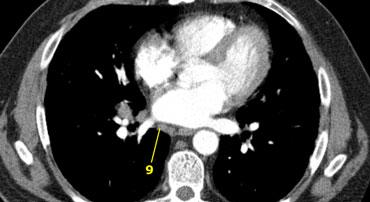

9. Hạch dây chằng phổi

Hạch dây chằng phổi nằm trong dây chằng phổi, bao gồm các hạch ở thành sau và phần dưới của tĩnh mạch phổi dưới.

Dây chằng phổi là phần kéo dài xuống dưới của các nếp gấp màng phổi trung thất bao quanh rốn phổi.